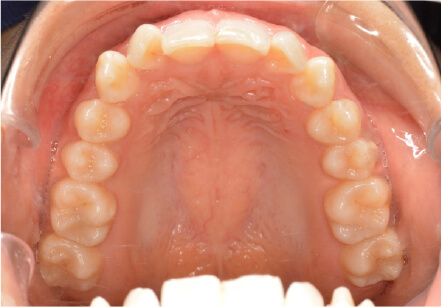

叢生の症例

9歳

/

男性

相談内容

ガタガタしているのが気になる

カウンセリング・診断結果

叢生。上3.3スペース不足。耳鼻科紹介

治療内容・方法

全額アライナー矯正

術後の経過・現在の様子

リンガルアーチ使用

治療のリスク

痛み・歯根吸収・歯肉退縮・虫歯・後戻り

費用・治療期間

140,800円、1年1ヶ月